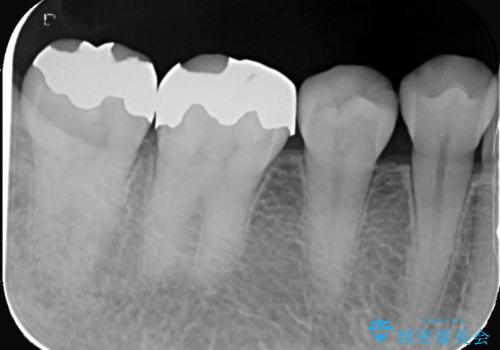

- 銀歯と歯の間に穴があり虫歯になっていました。

銀歯と虫歯を除去後、オールセラミッククラウンで治療を行いました。

銀歯のほとんどは錆びる金属で出来ています。

銀歯を外すと大小様々ですが、そのほとんどが虫歯になっていることが多いです。

今回も虫歯は大きく神経の近くまで広がっていましたが、神経は取らずに治療を終えることが出来ました。